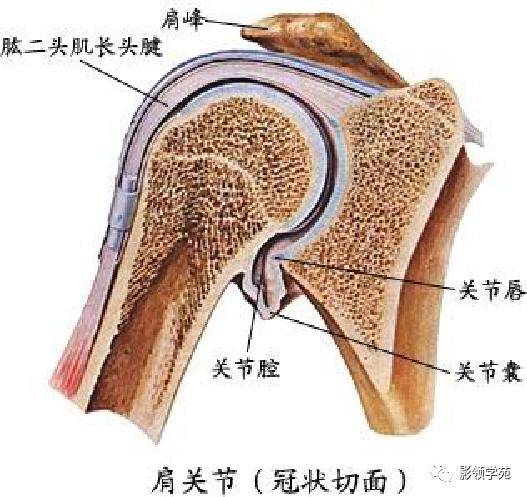

关节与韧带系统

关节与韧带系统